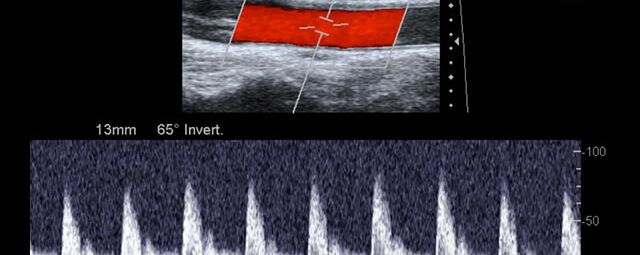

Die Sonographie ist ein bildgebendes Verfahren in der medizinischen Diagnostik, das mit Ultraschallwellen arbeitet. Ultraschall ist Schall mit einer Frequenz oberhalb der menschlichen Hörgrenze. Im medizinischen Bereich werden je nach Körperregion Ultraschallwellen in einem Frequenzbereich von ca. 3,5 – 18 Mhz verwendet. Die körpernahe Ultraschallsonde sendet durch einen piezoelektrischen Effekt kurze Schallwellenimpulse in den Körper. Ultraschall-Gel stellt den Kontakt zwischen Sonde und Körper her. Je nach Gewebeart werden diese Schallwellen im Körper unterschiedlich stark reflektiert. Anhand des zurückgesendeten Schallmusters kann das Ultraschallgerät Schnittbilder berechnen, auf denen die Organe des Körpers nach krankhaften Veränderungen untersucht werden können.